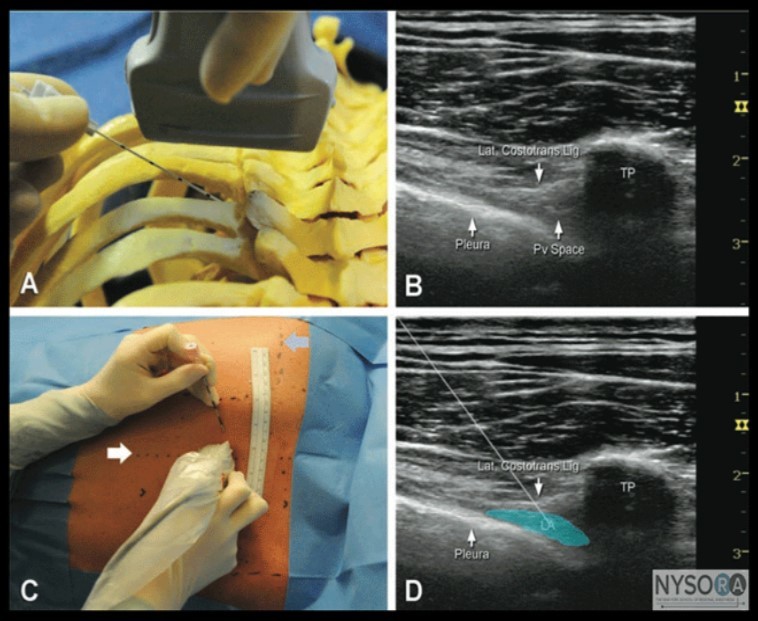

We must know that, Thoracic epidural and paravertebralblocks became the gold standard techniques to achieve this goal, but not every anesthesiologist is comfortable performing these procedures (Figure 4) 45.

Figure 4.U/S guided Thoracic epidural and paravertebral blocks 43

U/S guided Thoracic epidural and paravertebral blocks 43